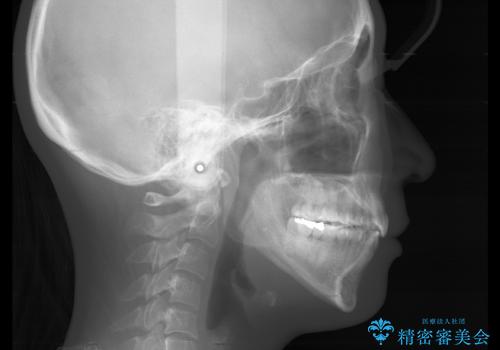

- 前歯を後ろへ下げることを主訴に来院された患者様です。

口元の突出感の改善や歯の移動量などを考慮し、抜歯を伴うワイヤー矯正での治療を選択しました。

抜歯を行うことで前歯を後ろへ下げるスペースを獲得し、口元の突出感や歯のガタつきを改善していきました。